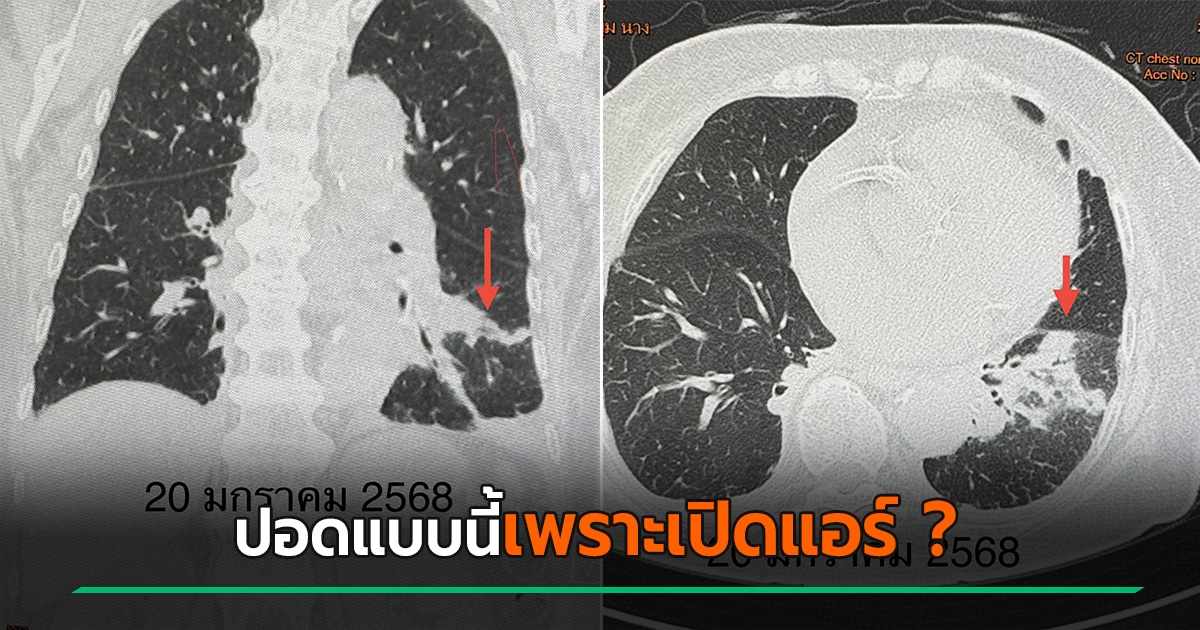

เปิดแอร์เข้าพักในคอนโด สุดท้ายปอดอักเสบ พอไล่หาสาเหตุถึงรู้ แอร์มีปัญหาตรงไหน